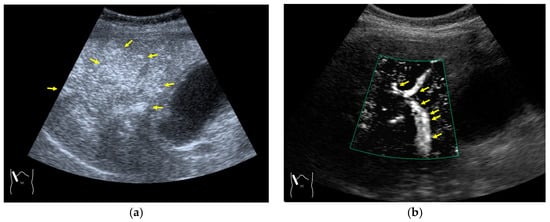

3.2.2. Prolonged Heterogeneous Accumulation Artifacts

Prolonged heterogeneous liver enhancement (PHLE) is a well-known CEUS artifact [28,55], and it is characterized by the appearance of “cloudy” or “wool-like” heterogeneous enhancements in the liver’s periphery [28,55]. PHLE begins to appear within 2–6 min after contrast injection (Figure 13). Despite having no clinical significance, this phenomenon has important negative impacts on CEUS diagnosis, as it mimics focal lesions [56], intrahepatic vascular anomalies [57], or portal vein gas [58]. Although there is no established mechanism for the appearance of this phenomenon, it is assumed that, as shown in Figure 12, the contrast agent that would normally flow through the portal vein as uniform granules and uniformly reach the hepatic periphery as non-uniform granules (due to contrast agent or other causes) in the hepatic periphery, and the areas with a high concentration of the large-diameter contrast agent are expressed as heterogeneously enhanced areas. However, the precise microcirculatory and basic mechanisms leading to this phenomenon remain only partially understood, and no satisfactory conclusions have been reached. However, the occasional inhomogeneity of the diameter of the contrast agent in the portal vein is clearly recognized in recent microflow imaging (Figure 13) [59]. Although detailed proof will require many experiments and clinical cases, we hope that microflow imaging will provide a new perspective that will help to clarify these artifacts. The most useful artifact avoidance strategy is to confirm the phenomenon’s instability by changing the examination conditions.

Figure 13.

Prolonged hyperenhancement. (a) CEUS image in the postvascular phase. Hyperenhanced areas (arrows). (b) Superb microvascular imaging reveals many aggregated bubbles passing in the portal vein (arrows).